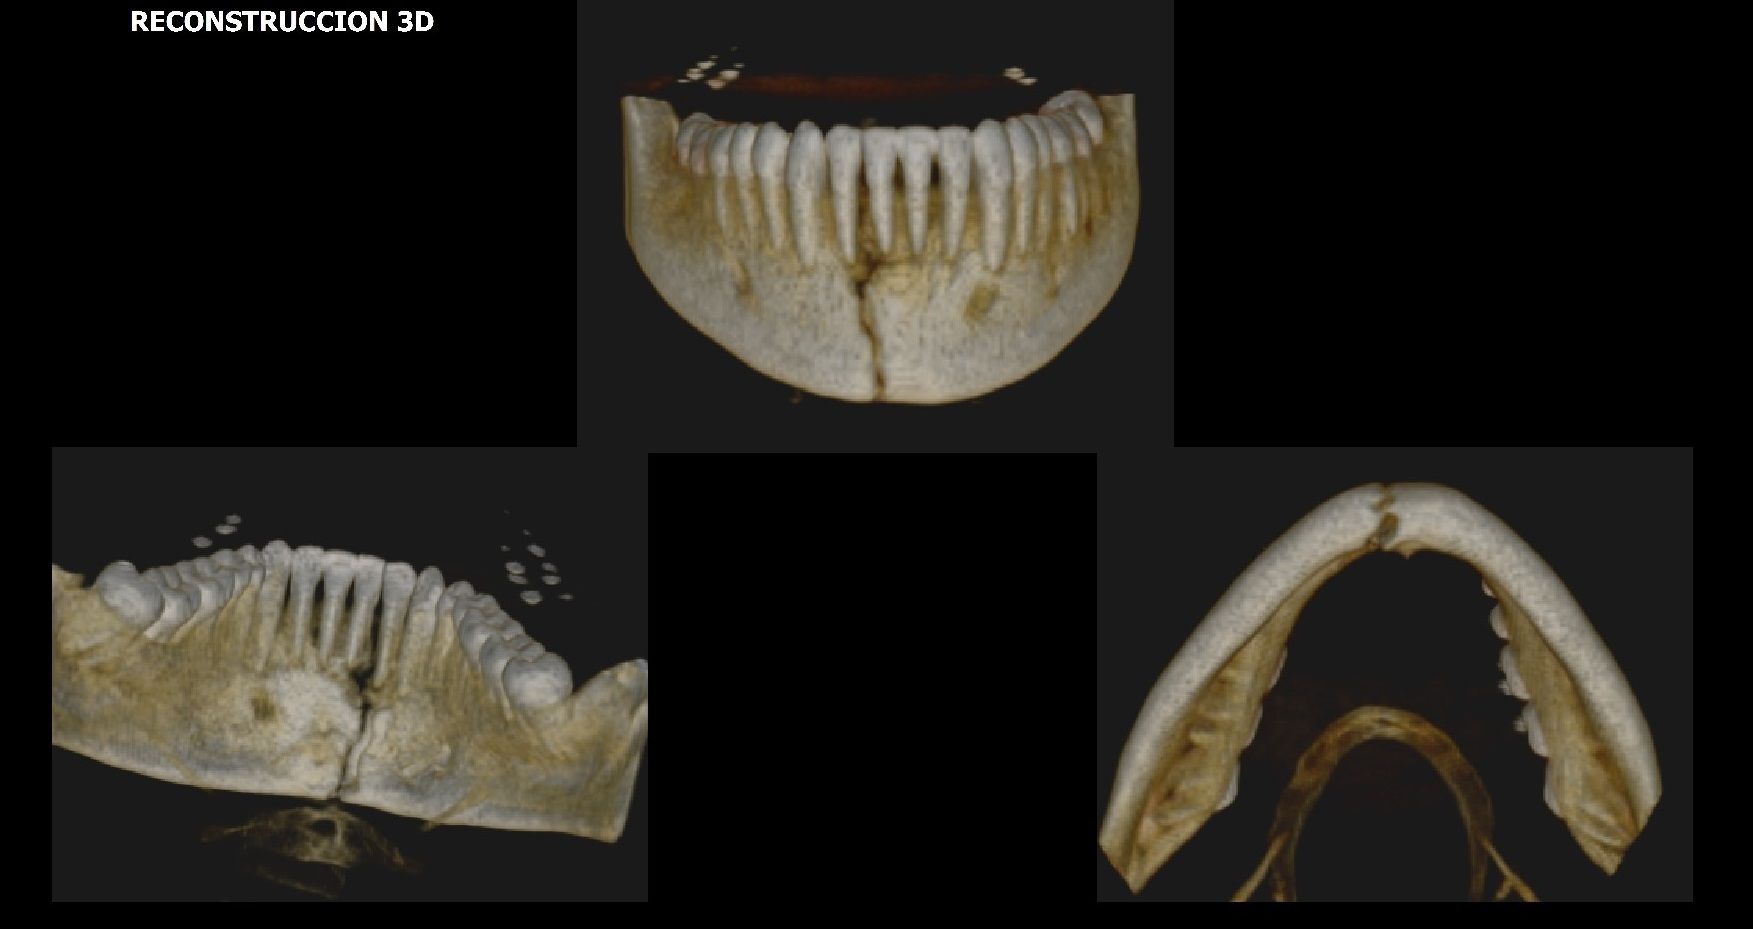

Contar con la más moderna tecnología permite una óptima visualización de piezas dentarias y estructuras óseas, articulares y musculares.

A las técnicas tradicionales como la radiología, sumamos estudios de avanzada para asistir a las prácticas de alta complejidad médica incluyendo la Tomografía Computada Cone Beam el más moderno sistema de imágenes odontológicas y maxilofaciales.